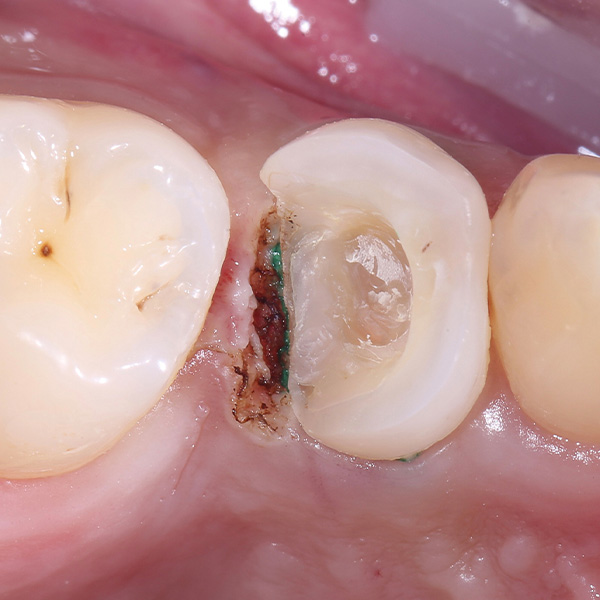

Bei der Versorgung von tief zerstörten, wurzelkanalbehandelten Zähnen mit Endokronen wird defektorientiert und minimalinvasiv vorgegangen. Im Gegensatz zu Präparationen für Vollkronen hat bei Endokronen der Substanzerhalt höchste Priorität. Dafür braucht es jedoch CAD/CAM-Werkstoffe wie das Hybridkeramikmaterial VITA ENAMIC, das in solchen Fällen sehr grazile Rekonstruktionen mit geringen Wandstärken ermöglicht und dessen Werkstoffeigenschaften ein zahnähnliches Verhalten aufweisen. Im vorliegenden Fall wurde die Hybridkeramik auch deshalb ausgewählt, weil sie sich aufgrund hoher Kantenstabilität präzise CAM-technisch verarbeiten lässt und eine sichere adhäsive Befestigung nach bewährtem vollkeramischem Protokoll ermöglicht.

Zahnärztin Dr. Oxana Naidyonova zeigt anhand des folgenden Fallbeispiels Schritt für Schritt ihre Vorgehensweise bei einer VITA ENAMIC multiColor Versorgung.